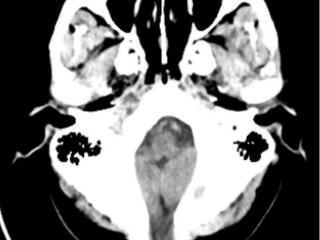

45年顽疾终得解!平邑县人民医院成功为先天性脑膜脑膨出患者解除困扰